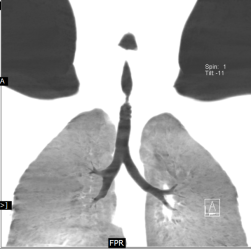

A 6-year-old female child presented to our clinic with progressive breathlessness and stridor for a duration of 5 days. She had a recent history of road traffic accident and sustained head injury and underwent craniotomy for extradural hemorrhage. Post-surgery she was on mechanical ventilator support for 10 days after which she was extubated. She developed stridor after 7 days of extubation. CT Neck revealed focal hour-glass configuration, concentric asymmetrical subglottic narrowing with associated soft tissue thickening 2-3cm below the level of vocal cords, with a diameter of 4.5 x 5.0 mm (AP X TR) at the point of maximal narrowing. Diagnostic flexible bronchoscopy showed circumferential stenosis (Grade III Myers-Cotton) of subglottic area about 2.5 cms below the glottis and we could not negotiate beyond the level of stenosis.

Rigid bronchoscopic repair of the stenosis was performed combining serial rigid bronchoscopic dilatations and balloon bronchoplasty using CRE dilatation balloons of varying sizes. Post dilatation, we were able to negotiate the rigid bronchoscope beyond the level of stenosis and were able to achieve a lumen of 100% with no residual stenosis. Follow-up CT Neck showed normal caliber of tracheal lumen with a luminal diameter of 8.6 x 8.3 mm at the level of previous narrowing. Total reduction of the clinical stridor was observed post procedure. Surveillance bronchoscopy after 4 weeks showed no further narrowing and good patency of tracheal lumen. Patient remained asymptomatic in subsequent follow up visits with improved pulmonary function tests

Radiology Images: